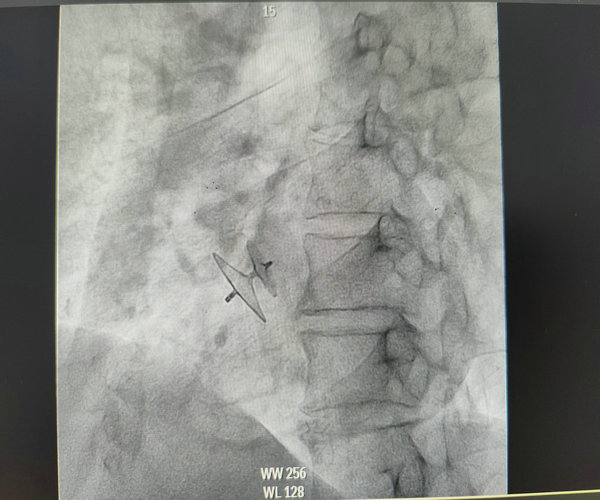

PFO封堵器释放成功